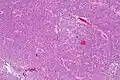

Микроскопически опухоль представляет собой хорошо дифференцированное новообразование с доброкачественными гистологическими особенностями. Опухоль состоит из «одинаковых клеток малого и среднего размера с округлыми ядрами, мелко пунктирным хроматином и незаметными ядрышками, а также скудной цитоплазмой». Опухоль характеризуются периваскулярными и похожими на пинеоцитоматозные псевдорозетками, которые напоминают цветы расположением клеток, с небольшим кровеносным сосудом в центре. Опухолевые клетки расположены плотно в некоторых областях опухоли, но другие области являются безъядерными, менее плотными частями опухоли. Безъядерные области могут иметь тонкий фибриллярный матрикс , как и в областях нейропиля. Длинные тонкостенные сосуды размером с капилляр являются сосудистой системой нейроцитомы. Эти сосуды линейно разветвляются и имеют эндокринный вид. Тонкостенные расширенные сосудистые каналы, а также очаги кальцификации встречаются часто.[11]

Малое увеличение

Среднее увеличение

Очень большое увеличение